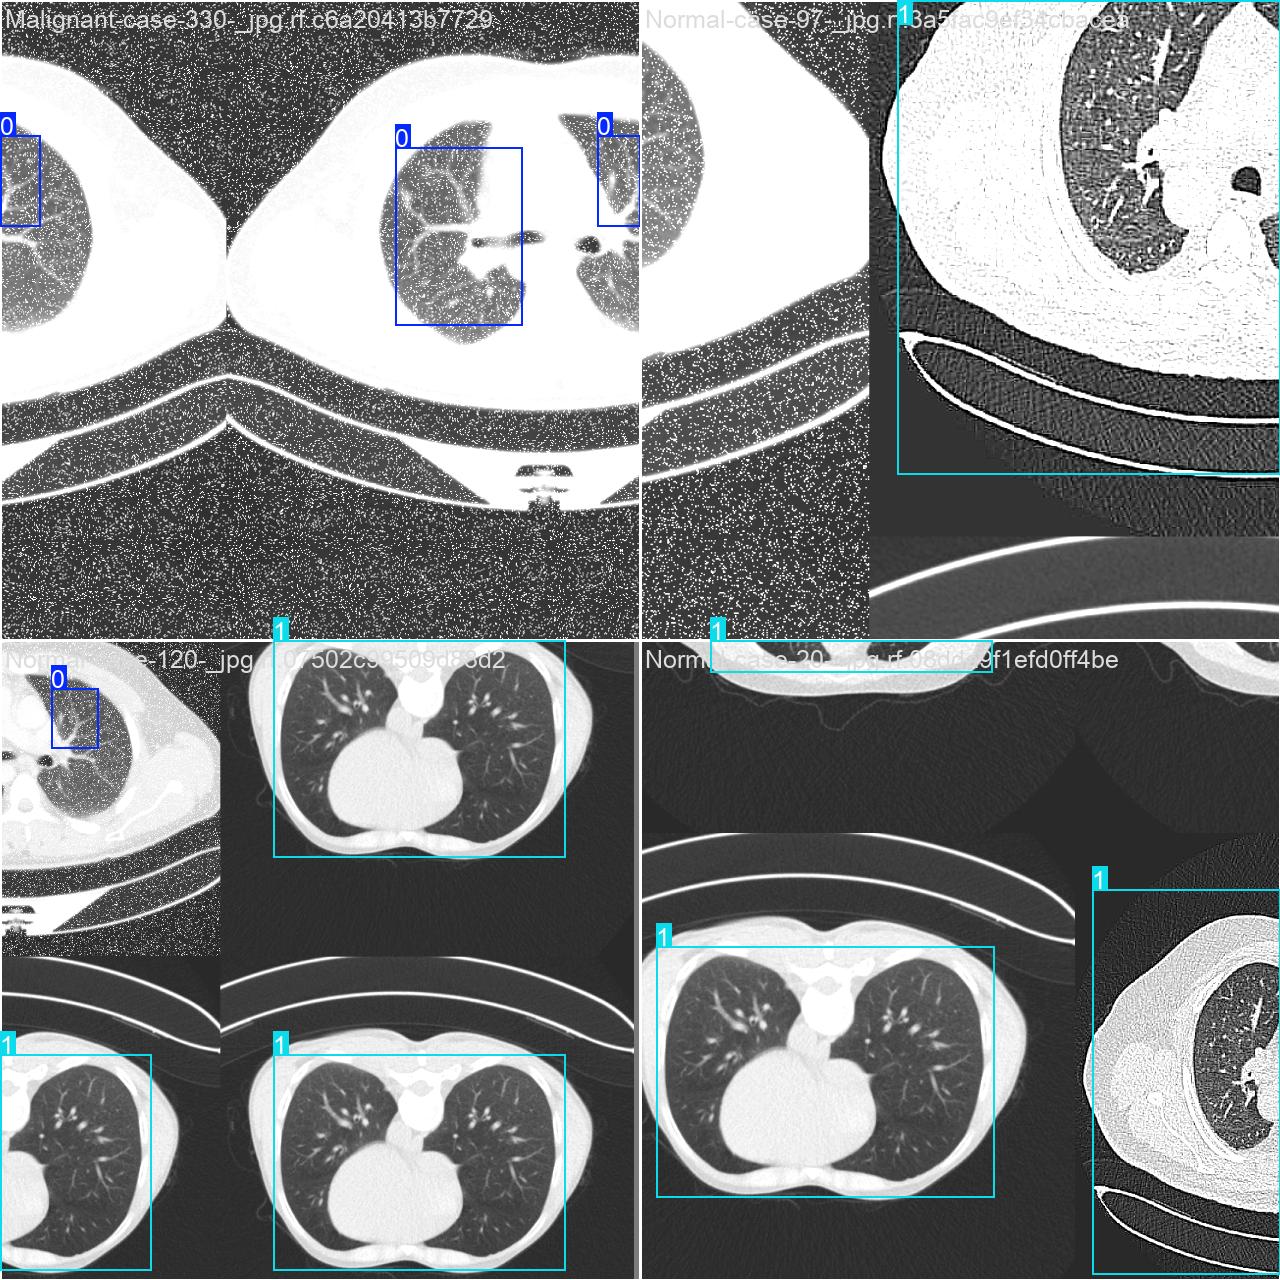

部分数据集图像如下图所示:

部分标注如下图所示: